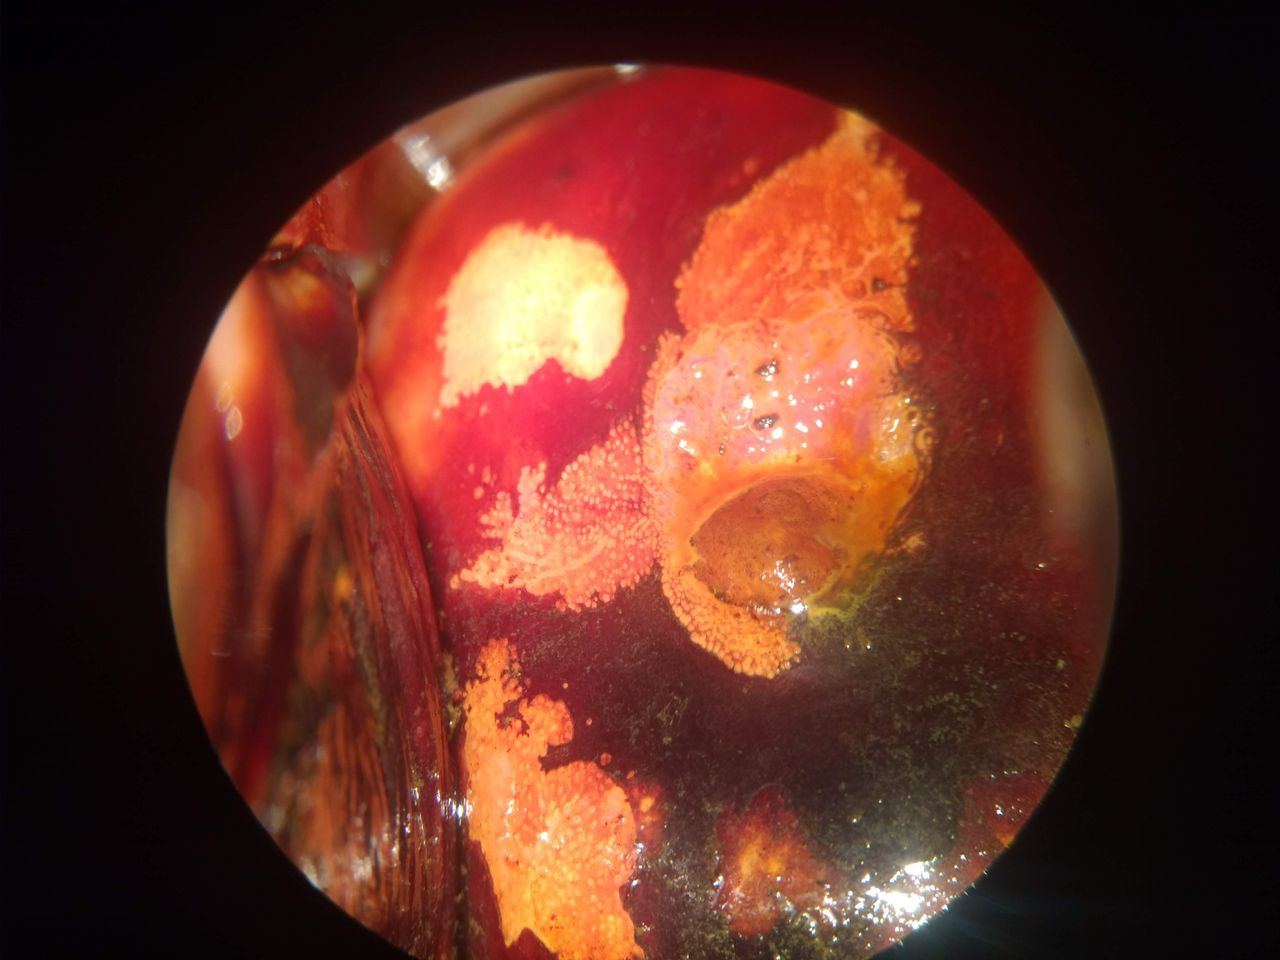

Somos expertos en el tratamiento de las lesiones por VPH, lesiones precursoras de cáncer del cuello uterino, entrenamiento en el extranjero para tratar parejas con VPH, androscopia (penescopia), anoscopia de alta resolución, electrocirugía, Infecciones de transmisión sexual ( chlamydia trachomatis, herpes, molusco contagioso), lesiones precursoras de cáncer en vulva y vagina), infecciones vaginales. Embarazo con condilomatosis genital Contamos con Prueba Molecular para VPH Contamos con Equipo de Electrocirugía

• Colposcopía y patología del tracto genital inferior

Fotos y videos